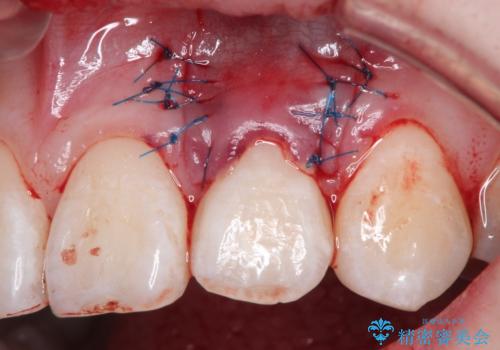

前歯の歯肉退縮 歯周形成外科(歯冠側移動術)

- 上顎左側側切歯の歯肉退縮を主訴に来院されました。

生活に支障はないが審美的要求が強く歯肉形成外科(歯冠側移動術)を行うこととしました。

根面被覆術には結合組織を用いる場合もありますが、今回のケースでは、角化歯肉が十分あり、審美性の要件が強いため、隣在歯との調和が取りやすい歯冠側移動術のみで対応しております。

結合組織を使用するメリットは術後の後戻りのリスクを減らすことが考えられます。